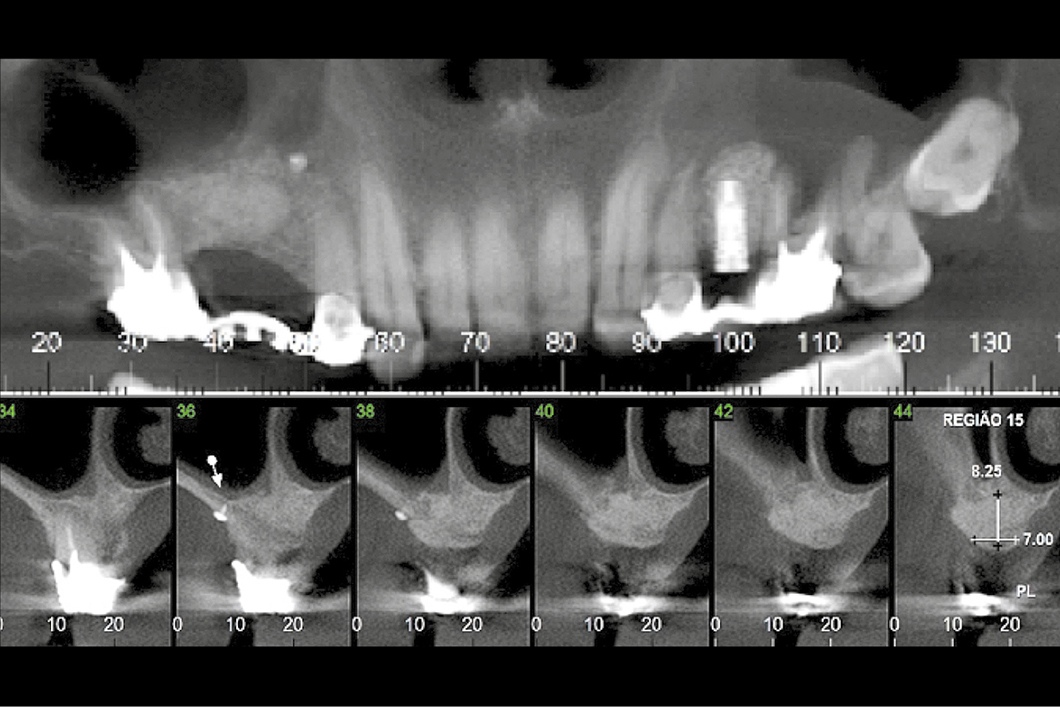

Ein schwieriger Fall einer oralen Rehabilitation mit einer besonderen Herausforderung in den Regionen 15 und 16. Der Patient hatte einige Jahre zuvor einen Autounfall gehabt und war in diesem Bereich verletzt worden. Dies führte zu einer anatomischen Veränderung des Sinus mit teilweisem Verlust der bukkalen Sinuswand und Narbengewebe in einem Teil des Sinus.

- Anspruchsvoll aufgrund der durch den früheren Autounfall verursachten anatomischen Abweichungen.

- Sinusboden-Elevation mit lateralem Fensteransatz in Kombination mit einer gesteuerten Knochenregeneration.

- Implantatinsertion 10 Monate nach Knochenaugmentation.

Während der Aufklappung wurde das Narbengewebe freigelegt und zum Teil entfernt. Nach diesem Schritt wurde eine Geistlich Bio‑Gide® Membran eingebracht, um das im oberen Teil der Sinushöhle vorhandene fibrotische Gewebe zu isolieren. Dann wurde die Schneidersche Membran in der mittleren Region des Sinus angehoben. Die Sinushöhle wurde mit Geistlich Bio‑Oss® gefüllt, das auch zur Regeneration des Kieferkammdefekts verwendet wurde. Geistlich Bio‑Gide® wurde bukkal mit Knochennägeln stabilisiert und unter den palatinalen Lappen gestopft.